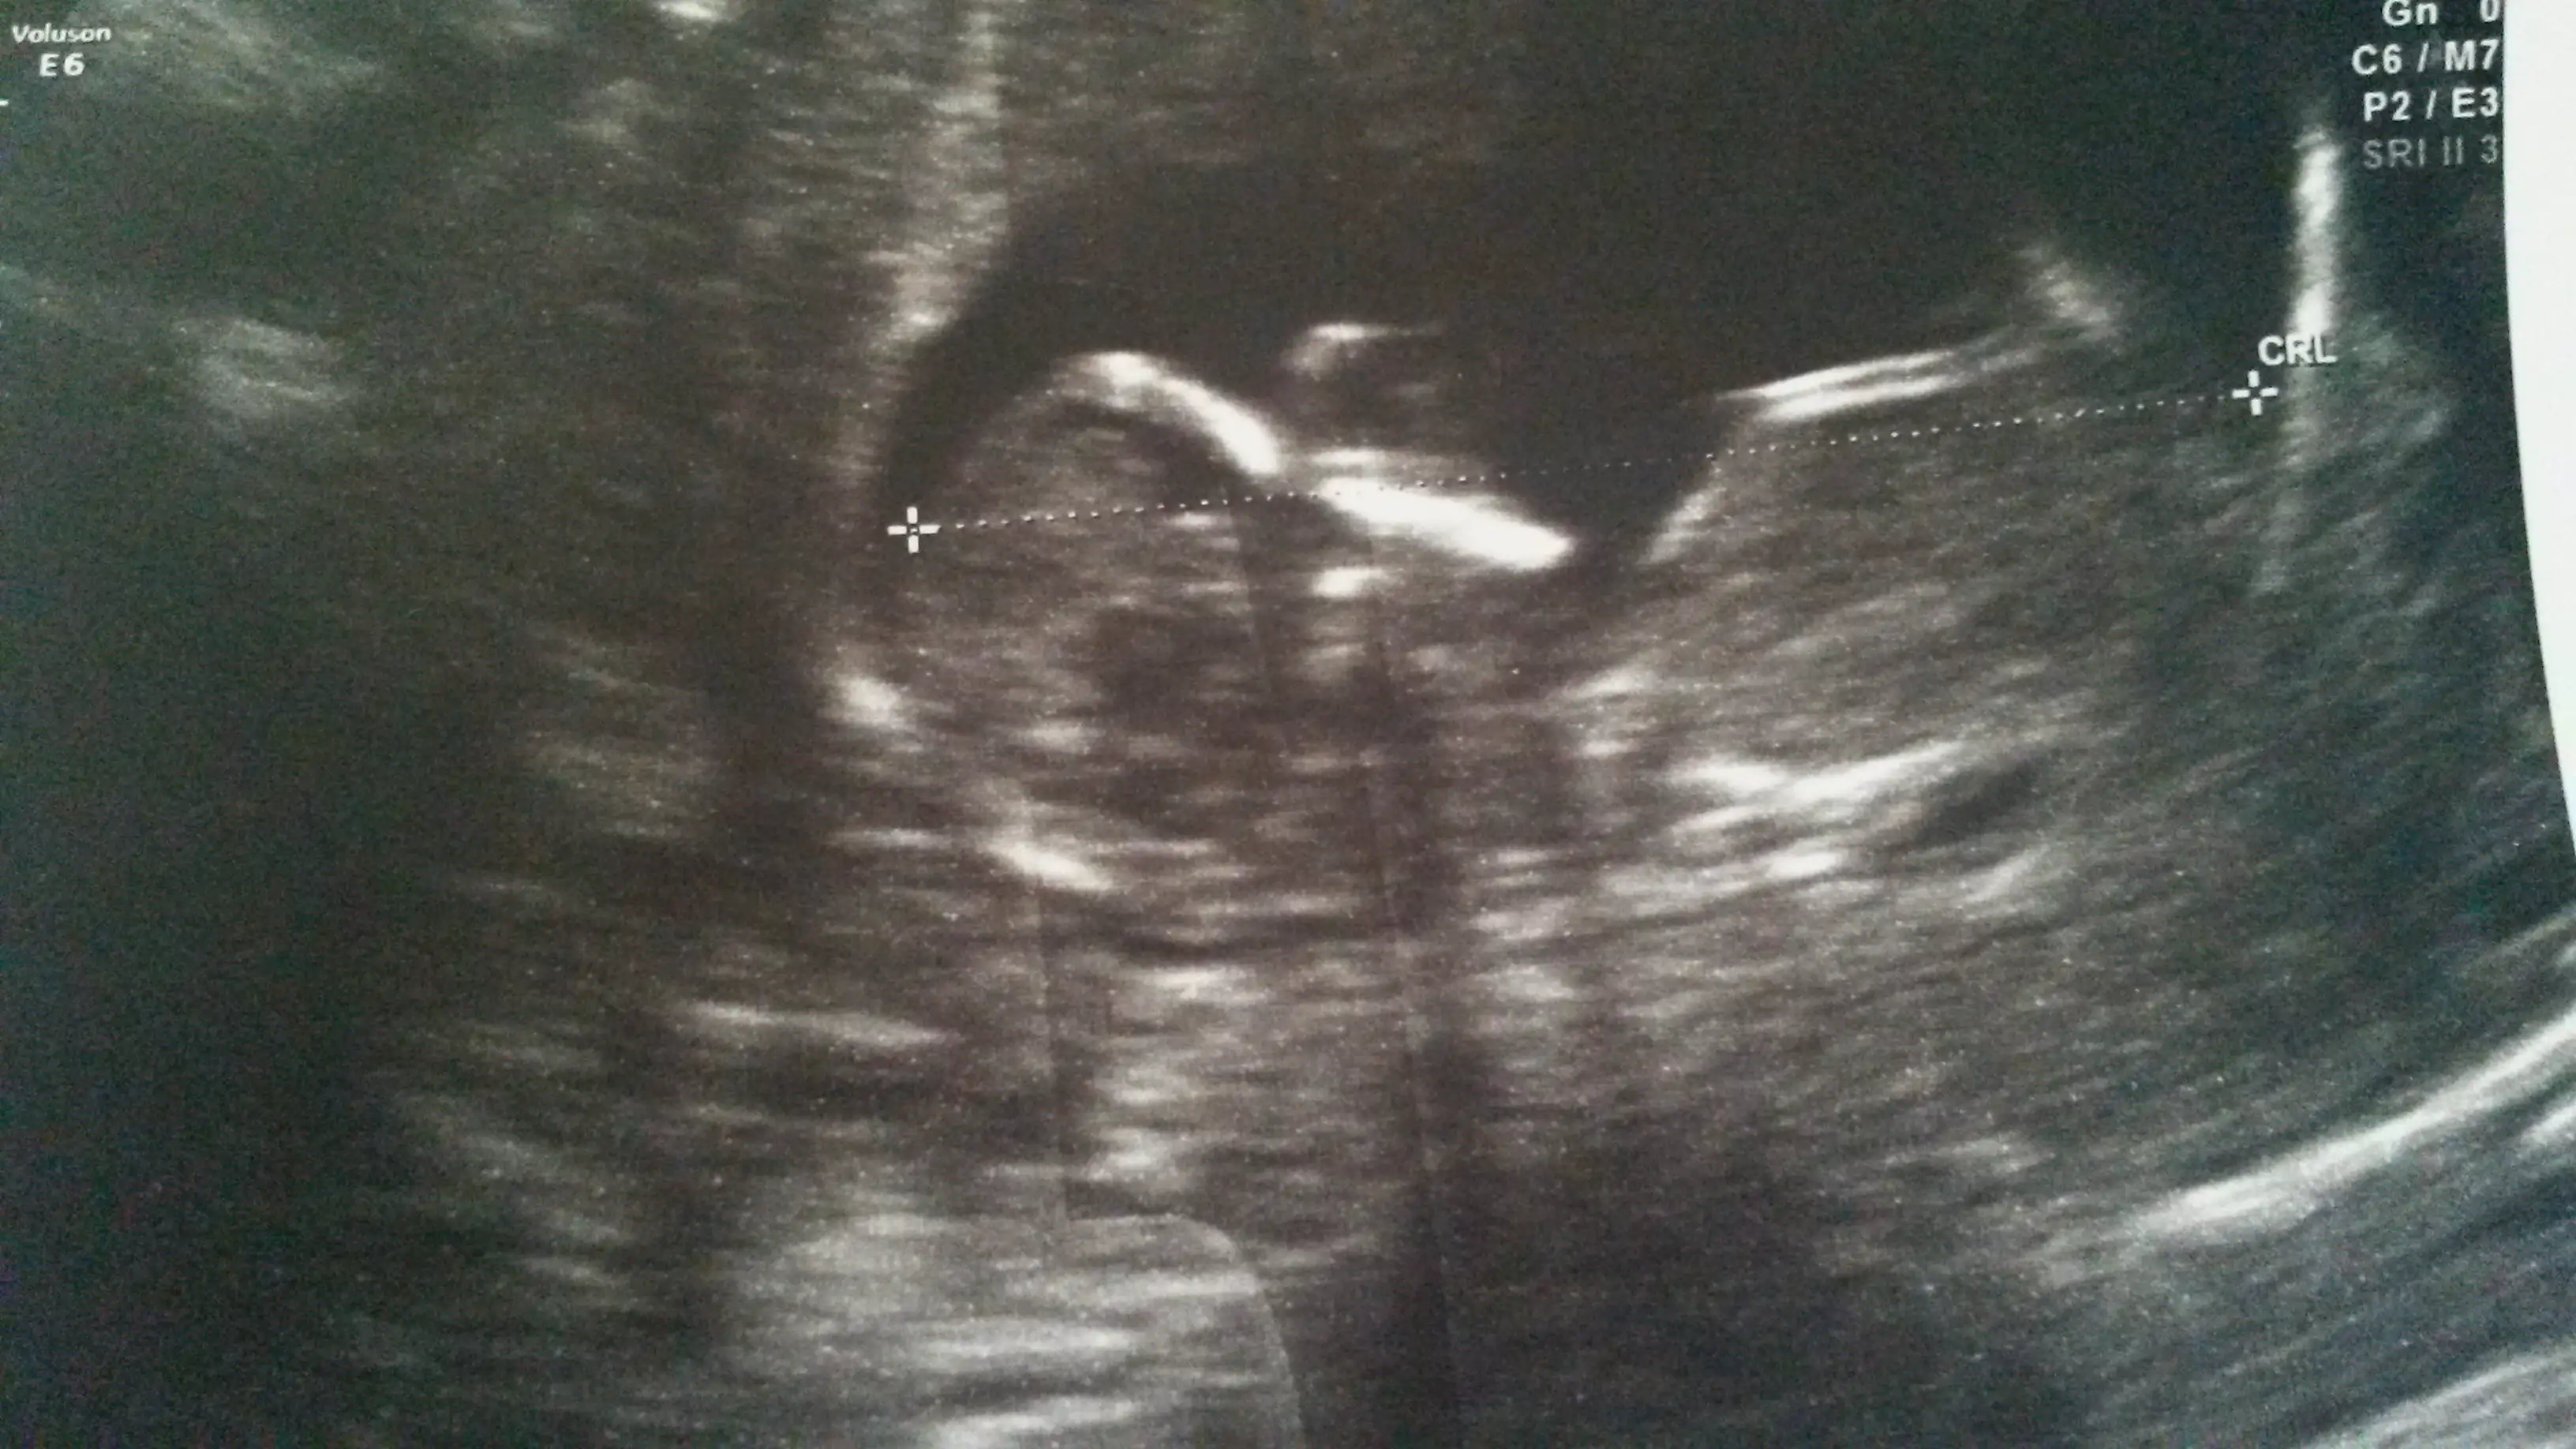

bu foto hiç net değil göremedim ama nub çok bitişik geldi bana öyle olunca erkek oluyo genelde rabbim hayırlısını ve gönlünüzdekini versinBuna bir yorum yapabilir misinizEki Görüntüle 1261426

nub için kötü bi pozisyon ama kıza benzettim benKızlar bizde dün 12+0a girdik. Çok merak ediyorum cinsiyetimizi ama dr birşey soylemedi biran önce ogrensekte öyle hitap etsek yavrumuza :) sizce tahminen nedir :)Eki Görüntüle 1260145

Benim bebiş te cinsiyetini göstermedi daha.tam net değil burda bi tahminde bulunabilir misinz? 12+3 günlüğüz burada